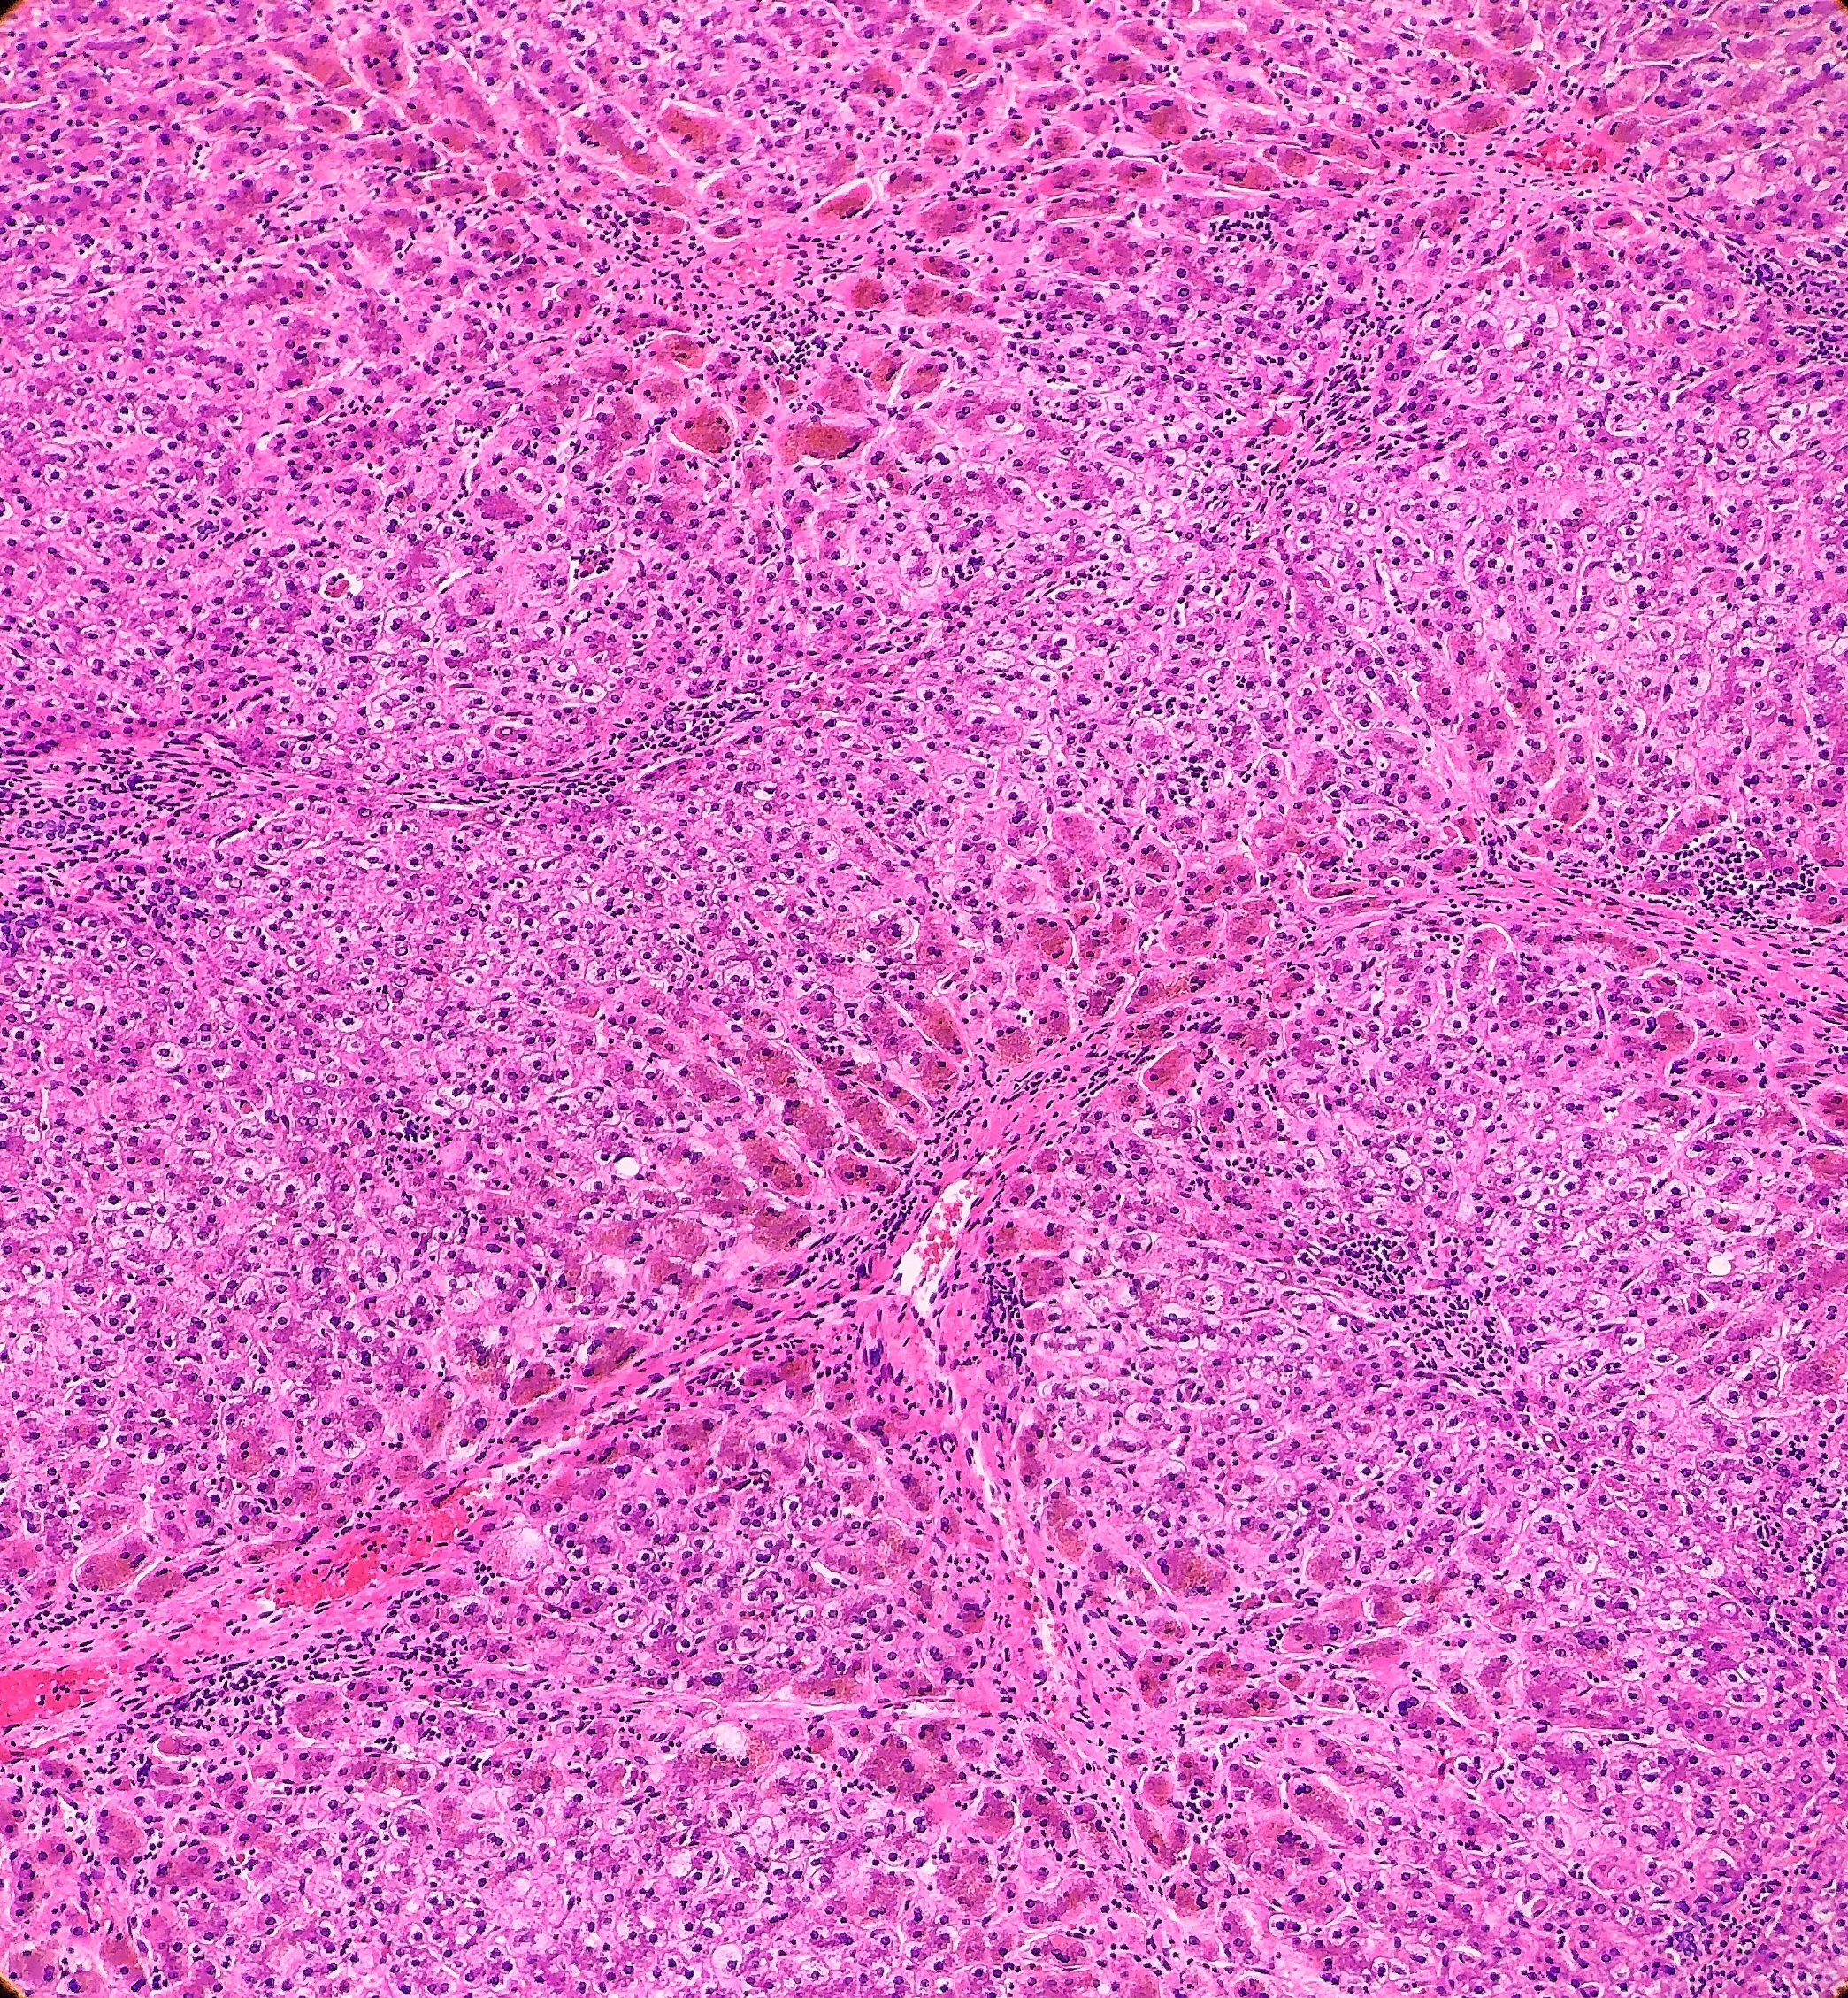

On microscopy, the trichrome stain highlights the presence of portal and centrilobular fibrosis, with focal bridging. However, regenerative nodule formation is not evident. The portal tracts contain sparse mononuclear cell infiltrates. Significant bile ductular proliferation is also evident, as confirmed by a CK7 immunostain. However, the native bile ducts appear unremarkable. There is also considerable hepatocellular and canalicular cholestasis in the centrilobular regions. Occasional multinucleated hepatocytes are also seen within the centrolobular zones. No steatosis is evident.

Histologically, PFIC1 and PFIC 2 will have canalicular cholestasis, an absence of true ductular proliferation, and periportal biliary metaplasia of the hepatocytes. In PFIC2, these manifestations are much more worrisome with more marked lobular and portal fibrosis, and inflammation, as well as having much more pronounced necrosis and giant cell transformation (Images 3 and 4). PFIC3 will show portal fibrosis and true ductal proliferation, with a mixed inflammatory infiltrate. In addition, cholestasis can be present in the lobule and in some of the ductules that contain bile plugs. Cytokeratin staining can help confirm the ductular proliferation within the portal tract. Mild or absent canalicular staining with BSEP and MDR3 antibodies will help to diagnose PFIC2 and PFIC3, respectively.